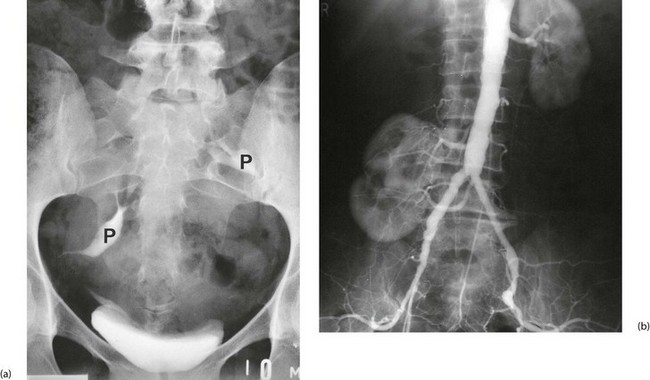

Fig. 39.5 Ectopic kidneys

(a) A 48-year-old woman with recurrent urinary tract infections; IVU shows abnormal pelvicalyceal systems P of bilateral pelvic kidneys.

(b) Right pelvic kidney discovered incidentally during arteriography for severe claudication. Its blood supply can be seen to arise from the distal aorta and iliac artery. The patient needed an aortofemoral bypass but when faced with the technical difficulties, agreed to conservative management of her claudication